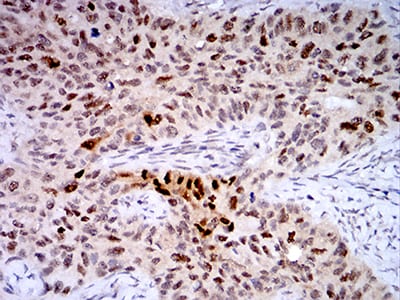

- Immunohistochemical analysis of paraffin-embedded human cervical cancer tissues using TTF1 mouse mAb with DAB staining.